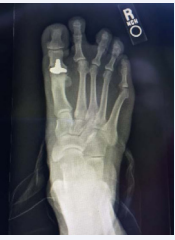

Before any treatments are offered a series of radiographs should be taken to assess the pathology of the first MPJ. This usually consists of the lateral, anteroposterior, and the medial oblique views of the affected foot. The AP view allows the practitioner to assess the joint space, while the lateral and MO views will show any associated spurring around the joint as well as the joint space. Occasionally loose bodies or sub chondral cysts are seen in any view taken. Sclerosis of the bone may also be seen on the radiographic studies since this is one of the ways that the bone tries to heal itself (Figure 1-4).

Figure 3: This is the radiograph of a patient whose initial surgery consisted of a hemi implant. The patient was not doing well with this type of implant and decided to undergo a second procedure and have it converted using the Arthrosurface total implant